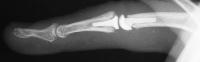

This gentleman presented with stiffness and lateral deviation of the ring finger proximal interphalangeal joint following volar plate arthroplasty for dorsal fracture dislocation.

Preoperative and postoperative radiographs.